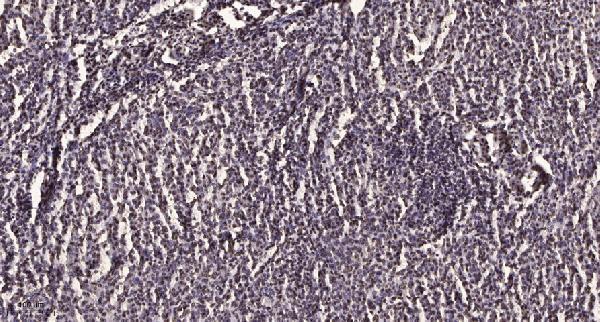

| Gene Name: | ZNF668 |